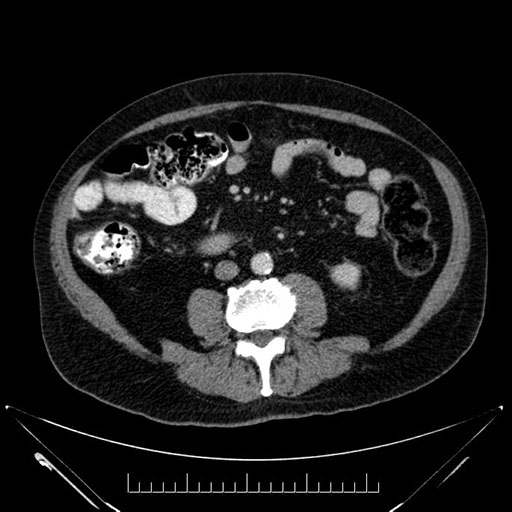

Imaging Analysis

Look through the patient's CT scan to identify any areas of concern for the necessary procedure.

Based on your CT findings, which issue(s) would give reason for "planned slowing down moment(s)" in this case?